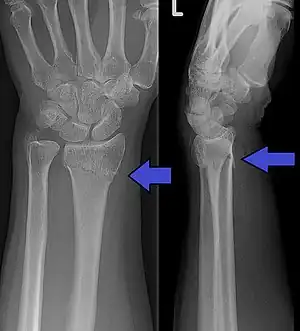

The classic Colles fracture has the following characteristics:[7]

- Transverse fracture of the radius

- 2.5 cm (0.98 inches) proximal to the radio-carpal joint

- dorsal displacement and dorsal angulation, together with radial tilt[8]

- Radial shortening

- Loss of ulnar inclination≤

- Radial angulation of the wrist

- Comminution at the fracture site

- Associated fracture of the ulnar styloid process in more than 60% of cases.

Bilateral Colles fractures/frontal

Bilateral Colles fractures/lateral